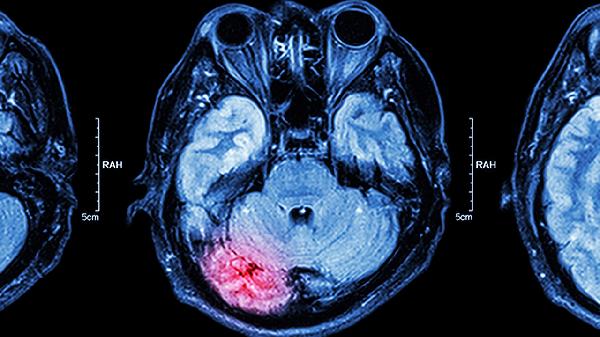

2、脑结构异常

影像学检查可见患者脑室扩大、前额叶体积减小等改变,可能与孕期感染、缺氧等导致神经发育异常有关。这些结构变化会影响认知功能和情绪调节,表现为工作记忆下降、执行功能障碍等前驱症状。早期发现脑功能异常可通过认知训练进行干预。